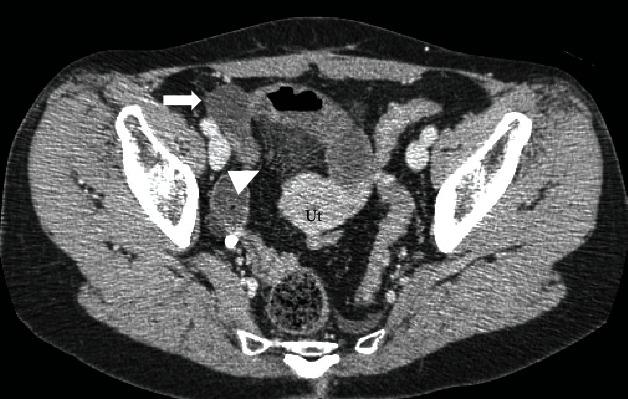

Herniation through a defect of the uterine broad ligament is a rare internal hernia that is difficult to diagnose definitively. Common hernia contents contain ileal loops. Herein, we report a rare case of internal herniation of both the ileum and fallopian tube through a defect of the broad ligament. A 52-year-old woman presented to our hospital with suprapubic pain and vomiting. She had a history of bowel obstruction following cesarean section. On abdominopelvic computed tomography, we suspected a closed-loop obstruction associated with bowel herniation in the right broad ligament. However, we could not identify an area of poor enhancement adjacent to distended small intestines. Emergency laparoscopic exploration revealed a viable ileal loop and incarcerated organ. Therefore, we switched to laparotomy that revealed the right fallopian tube as the ischemic organ. We reduced the hernia, resected necrotic right fallopian tube, and closed the defect of the broad ligament. The patient had an uneventful postoperative course. Rare hernia contents might complicate preoperative clinical diagnosis. Laparoscopy is useful for establishing a definitive diagnosis and treating broad ligament hernias.